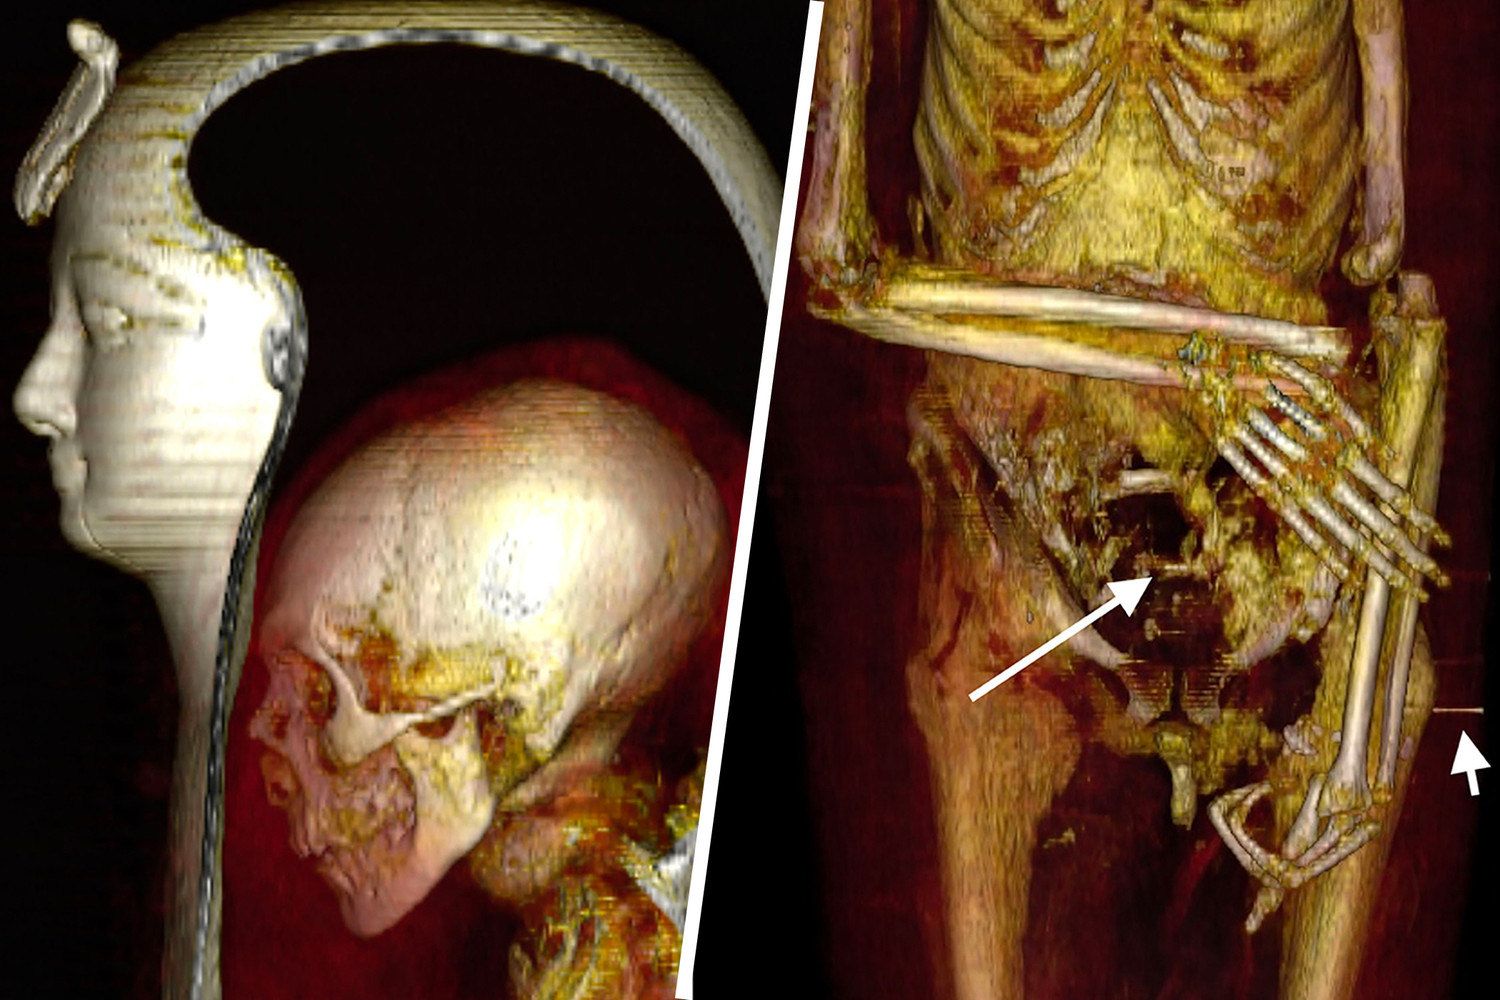

Мумию египетского фараона Аменхотепа впервые смогли рассмотреть египетские ученые с помощью компьютерной томографии. Удалось выяснить, что фараон был обрезан, его рост составлял 168,5 см, на момент смерти Аменхотепу было 35 лет. Спустя несколько веков после захоронения в его гробницу наведались грабители и в поисках сокровищ поломали мумии кости, но бальзамировщики сделали все возможное, чтобы восстановить тело. Исследователи надеются, что в будущем удастся подобным образом, не разматывая бинтов и не снимая масок, рассмотреть мумии и других правителей Египта, узнав больше об их анатомии, возможных болезнях и причинах смерти.

Также КТ позволила лучше рассмотреть лицо мумии — овальное, с впалыми глазами и обвисшими щеками.

Нос маленький, узкий, приплюснутый. Верхние зубы слегка выступают. Подбородок узкий. Уши маленькие, левое проколото. На затылке сохранились несколько вьющихся локонов. Возможно, эти данные можно будет использовать для реконструкции лица фараона.

Исследователи обнаружили у Аменхотепа множество травм, но все они оказались посмертными: переломы шеи и позвоночника, вывихи и переломы рук, перелом лобковой кости. На одной из рук отсутствуют два пальца, они уложены в районе живота мумии. По всей видимости, мумия пострадала от рук расхитителей гробниц.

Мозг перед мумификацией не извлекался — он сохранился в черепе. Сам череп тоже был нетронут. Но внутренние органы были удалены через отверстие в боку, через него же тело было набито тканью. Сердце осталось на месте.

При повторном захоронении мумию явно пытались «отремонтировать» — пропитанные смолой бинты фиксировали оторвавшуюся из-за перелома шейных позвонков голову, прикрывали повреждения брюшной полости. Сломанным и вывихнутым конечностям придано подходящее положение. Ступни зафиксированы с помощью деревянных дощечек.